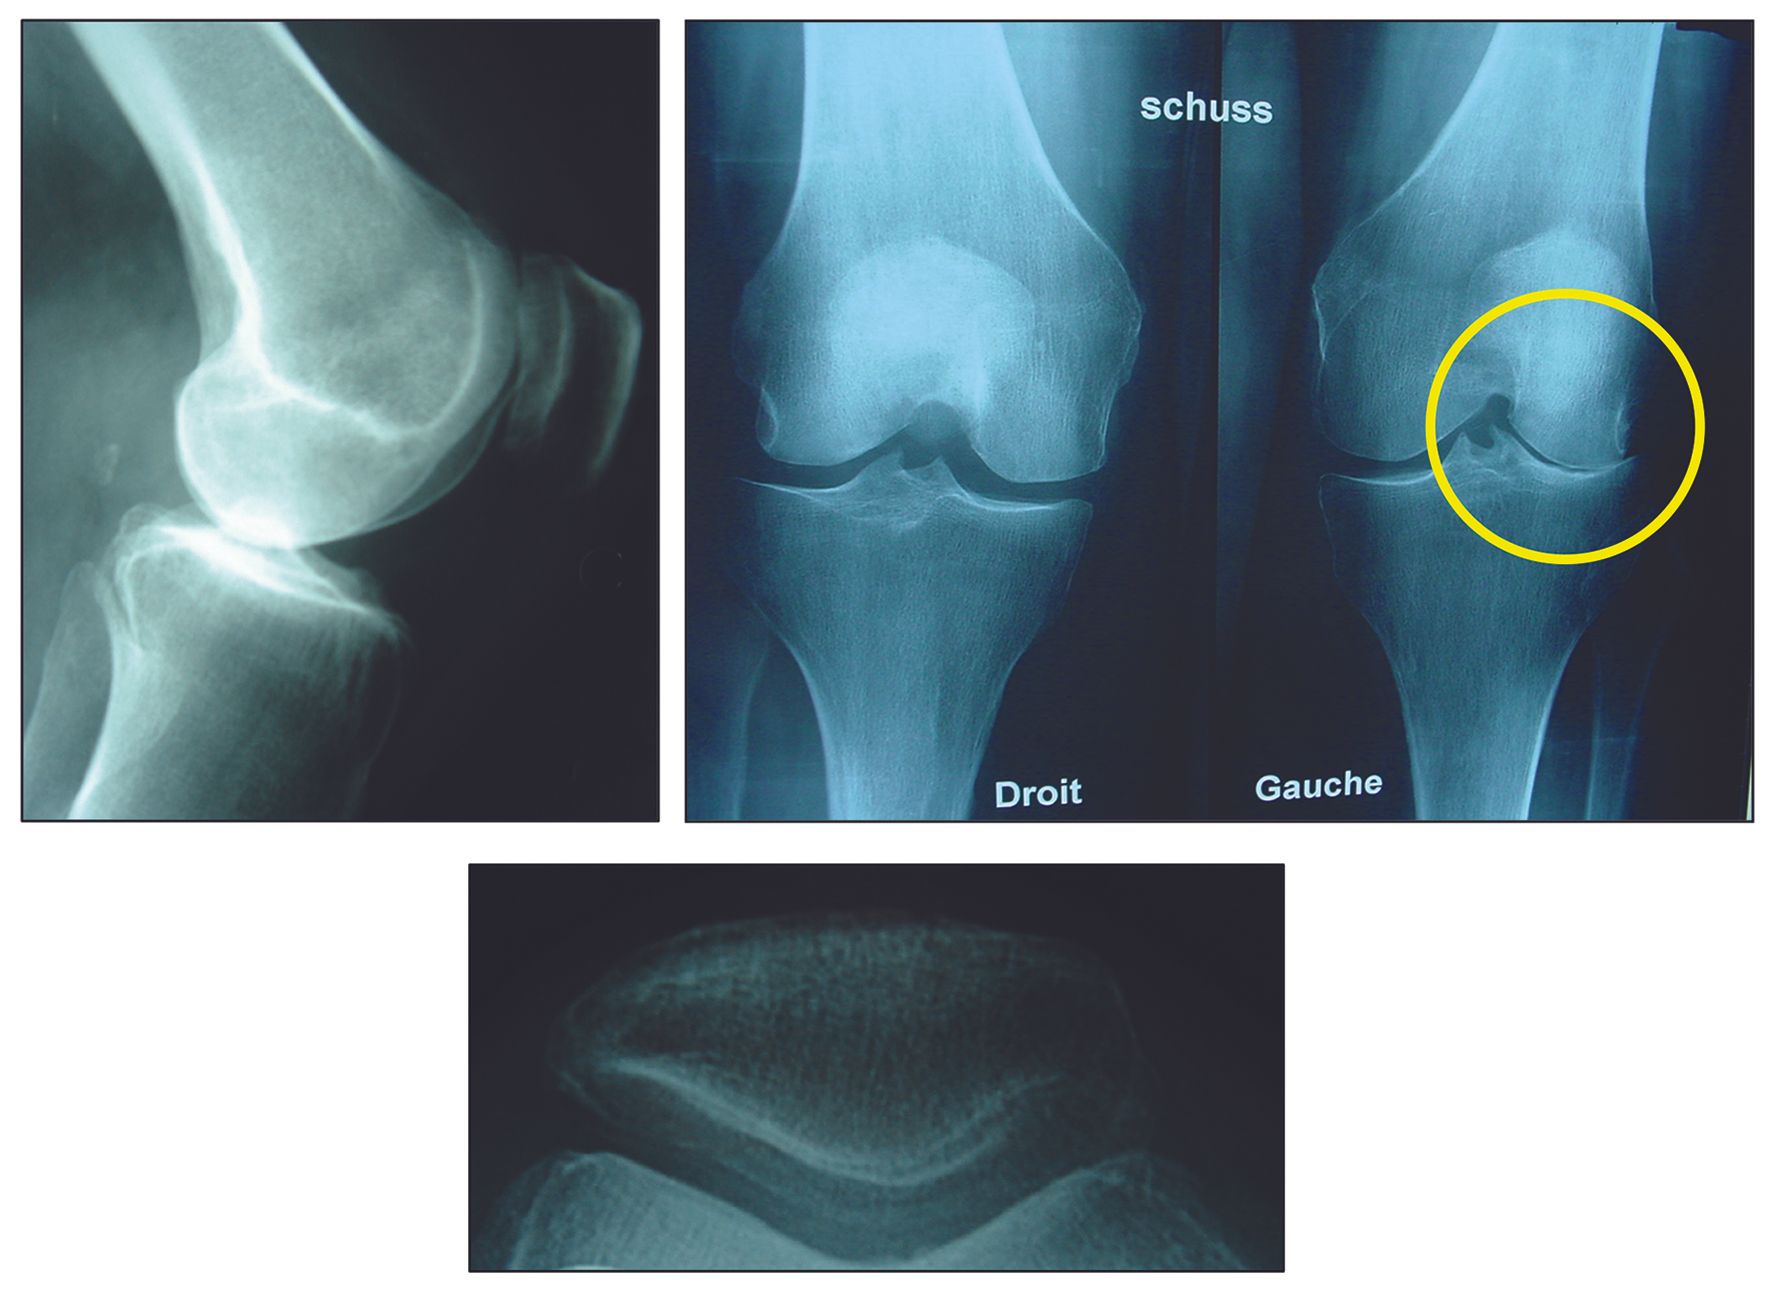

The clinical and scientific articles in this issue address both technical and organizational dimensions of arthroplasty. Component rotational alignment in total knee arthroplasty is critically examined alongside strategies for optimizing efficiency in the operating theater. Lateral unicompartmental knee arthroplasty with mechanical instrumentation is explored with attention to long-term outcomes, while bearing options in total hip arthroplasty offer guidance for surgical decision-making. The EKS and ICJR Partnership and a critical review of robotic TKA surgery further contextualize the evolving institutional and technological landscape.